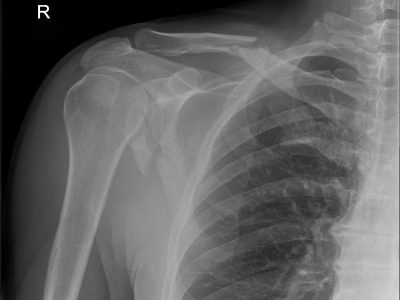

Τα κατάγματα και εξαρθρήματα στη περιοχή του άνω άκρου αφορούν τη περιοχή του ώμου δηλαδή τα οστά του βραχιονίου, ωμογλήνης, κλείδας και ωμοπλάτης. Επιπλέον αφορούν το υπόλοιπο βραχιόνιο, τις 3 αρθρώσεις του αγκώνα, το αντιβράχιο, τη πηχεοκαρπική, τα μικρά οστά του καρπού καθώς και τα μετακάρπια και τις φάλαγγες των δακτύλων.

2. Αντιμετώπιση σύνθετων καταγμάτων βραχιονίου, ωμογλήνης, ωμοπλάτης και κλείδας.

Παρακάτω παρατίθενται ακτινογραφίες καταγμάτων του άνω άκρου που αντιμετωπίζονται με εσωτερική οστεοσύνθεση ή επανορθωτική χειρουργική με αρθροπλαστική.